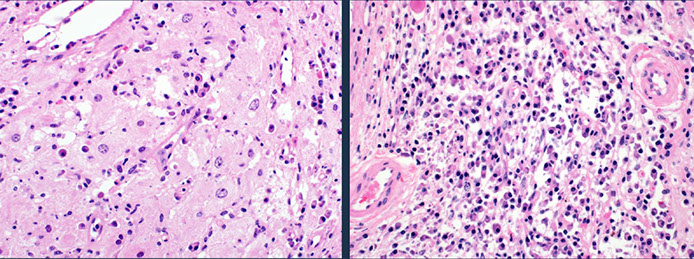

Infectious mono can look like DLBCL

Paracortical hyperplasia, paracortex with moth-eaten appearance and has lots of lymphs which can be small to large sized, as well as immunoblasts, histiocytes and plasma cells

Late: prominent paracortical hyperplasia with numerous scattered immunoblasts and hypervascularity

Micro:

- expanded paracortical area

- sheets and clusters of immunoblasts may mimic DLBCL

-- these immunoblasts are CD30+, CD15-, ALK1 neg, EMA neg, CD45+ and EBV+, and some are T-cells (PAX5+) and some are T-cells (CD3+)

Upper left shows scattered reactive follicles, upper right shows fairly well-differentiated mantle zones, lower left shows aggregates of monocytoid B-cells (small cells) in the paracortical region, and the lower right is a somewhat atypical immunoblastic cells (would stain positive for EBV ISH)

High-powered view of monocytoid B-cells (MBCs) in infectious mono, which have slightly irregular, almost centrocyte-like nuclei with abundant pale cytoplasm and some interspersed neutrophils

Features of infectious mono, all cases showed architectural distortion, but showed areas of preserved architecture, which often merged with more abnormal areas

Infectious mononucleosis with areas of preserved architecture with reactive follicles, patent subcapsular sinuses, and intact capsules. Despite relative hyperplasia of paracortex, always has areas of preserved normal architecture

Infectious mononucleosis. Admixed population of cells of varying sizes. In areas where immunoblasts predominated (right) which could be a florid expansions, like large aggregates or sheets of cells with mitotic activity. Spend some time on low power to appreciate the normal architecture, try to find areas with a variety of cell types. Immunoblasts may resemble Reed-Sternberg (RS) cells (inset). [3]